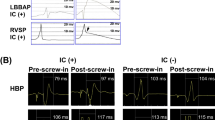

We performed in silico computer modelling [13] to assess the effect of RVAP and RVSP on endocardial and epicardial activation. A patient-specific mesh of a heart failure patient who underwent CRT was created from segmented MR images, as described previously [13]. Intrinsic LBBB was modelled by activating the RV at the anterior endocardial free wall [14], with a fast endocardium layer in the RV [15]. Simulations of RVAP at the anterior, posterior, and mid regions of the RV apex and RVSP were also modelled. The spread of the electrical activation across the ventricles for the 5 different scenarios (LBBB, 3 RVAP, RVSP) was simulated using the Cardiac Arrhythmia Research Package (CARP) [16].

3.2 In silico modelling

The activation times were normalized with respect to the VVtat (biventricular total activation time). The Pearson correlation of the activation times across the mesh was then calculated for the intrinsic LBBB model in comparison with the three RVAP and RVSP simulations. Consistent with the observations seen in the patient studies with electroanatomical mapping in the clinic, it was found that the RVSP simulation had a higher correlation to the LBBB simulation in comparison with the RVAP simulations at the anterior, middle, and posterior sites at the RV apex (81% vs 26–73%) (Fig. 5). The latest activation region in the LV free wall did not shift significantly with RVSP (1 mm); however, RVAP caused a change in the latest activation region by 10–41 mm.

The spread of electrical activation was simulated in intrinsic LBBB, pacing at the RV apex at anterior (RVAP-A), middle (RVAP-M) and posterior (RVAP-P) sites, and pacing at the mid wall of the RV septum (RVSP). The latest activation regions (black circles) are shown on the 16 segment American Heart Association models of the activation across the LV epicardium and endocardium

- 6.

These changes were consistent with the in silico modelling with a higher correlation between the intrinsic LBBB model when pacing at the mid septal wall in the RV than when pacing at the mid, anterior, or posterior RVA (81% vs 73%, 26% or 26%). The latest activation region in the LV free wall did not shift significantly with RVS pacing (1 mm); however, RVA pacing caused a change in the latest activation region by 10–41 mm.

4.4 In silico modelling

The results of the in silico model are in keeping with the results from patients undergoing non-invasive mapping. The model predicts that RV septal pacing will produce an activation pattern in the left ventricle which is similar to intrinsic LBBB whereas apical pacing resulted in a differing pattern of activation.